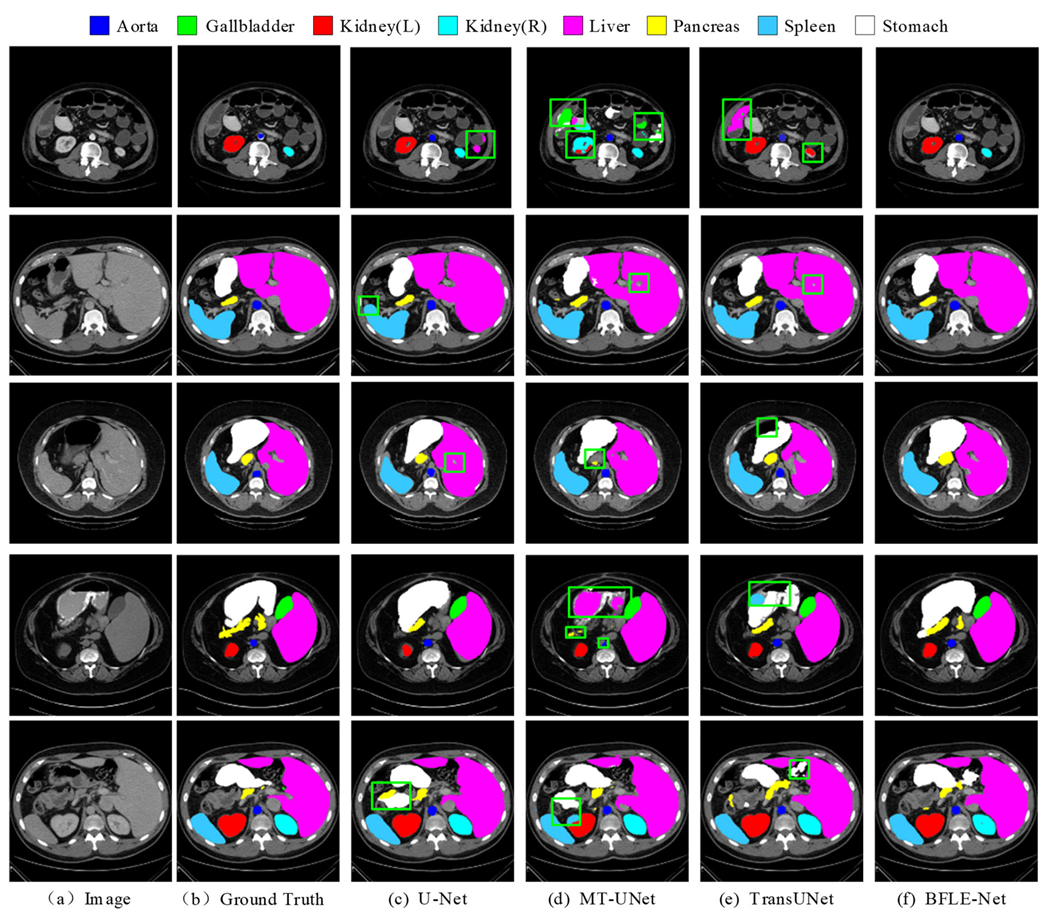

To evaluate the performance of the proposed approach, we use two publicly accessible medical image segmentation datasets—the Synapse dataset and the ACDC dataset. See Table 1 and Figure 5 for details.

Here are 30 abdominal CT scans in the Synapse dataset. Annotations of eight organs—liver, pancreas, spleen, stomach, right and left kidneys, aorta, and gallbladder—are included in the dataset, which consists of 3779 axial slices of abdominal CT scans. Every slice is 512 × 512 pixels in size. In this case, with reference to the TransUNet literature, the slices from 18 cases were used as the training set, and the remaining 12 cases were reserved for testing and evaluation.

Each of the 100 sets of cardiac magnetic resonance images in the ACDC dataset was annotated by a specialist with knowledge of the left atrium, right ventricle, and myocardium. In this investigation, we adhered to the data partitioning approach utilized in TransUnet, segregating the dataset into 70 cases for training, 10 for validation, and 20 for testing.

Figure 5. Pictures of the selected datasets are shown.

Electronics 14 03054 g005